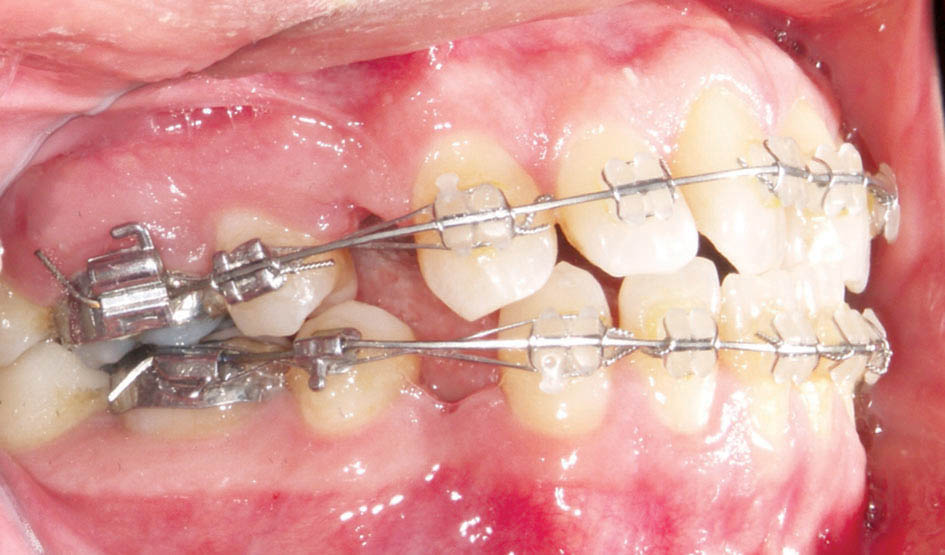

بعد از مرتب شدن قدامیها سیم را ضخیم میکنیم. سیم 0.016 حرارتی را خارج و دندانهای قدامی را با سیم لیگاچور figure ∞ میکنیم و سیم 0.019x0.025 حرارتی را میگذاریم. اگر قدامیها را با سیم لیگاچور نبندید احتمال ایجاد فضا بین دندانهای قدامی وجود

دارد (شکل 18-3). ماه بعد مرحله Releveling را داریم.

شکل 18-3: اگر براکت دندانهای قدامی را در زمان سیم 0.019x0.025 حرارتی figure ∞ نکنید احتمال بروز فضا بین دندانی وجود دارد.